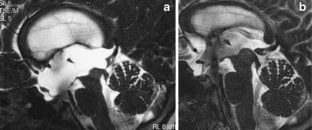

Tisell M, Edsbagge M, Stephenson H, Czosnyka M, Wikkelsø (2002) Elastance correlates with outcome after endoscopic third ventriculostomy in adults with hydrocephalus caused by primary aqueductal stenosis. Neurosurgery 50:70–77

Fukuhara T, Luciano M (2001) Clinical features of late-onset idiopathic aqueductal stenosis. Surg Neuro 55:132–137

Harrison MJG, Robert CM, Uttley D (1974) Benign aqueductal stenosis in adults. J Neurol Neurosurg Psychiatry 37:1322–1328